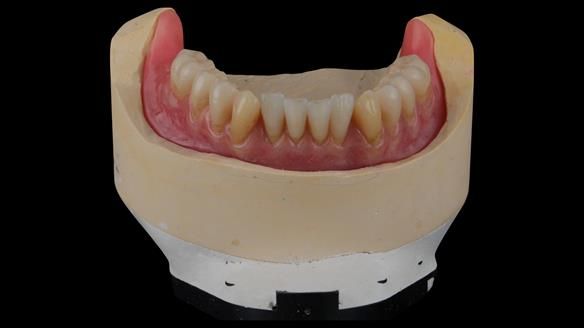

Provision of metal reinforced complete dentures. The lower can be converted to implant support in the future, if needed.

Following consultation, the patient chose to have replacement upper and lower conventional metal reinforced dentures made (professional fee £7,978 GBP). Metal reinforcement was given because of a history of breaking dentures. The lower denture was designed to allow conversion to an implant supported over denture if required (additional fee £12,542 GBP).

The clinical situation and treatment process is shown in detail below with photographs. I (Finlay Sutton) provided the clinical work and Rowan Garstang provided the technical work.